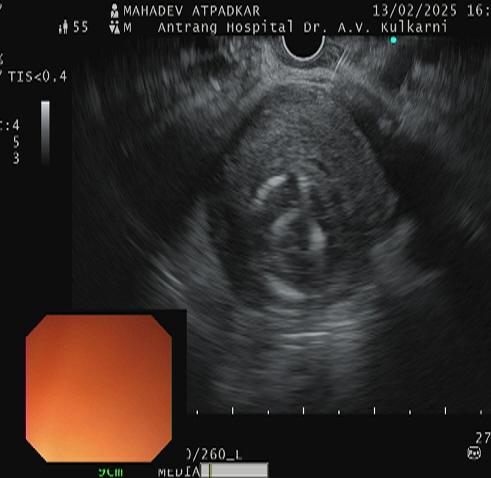

A 53 years- old male presented with a history of repeated GI bleeding for 20days. He had undergone UGI scopy and colonoscopy twice elsewhere with no obvious source of bleed. He was referred to us for further management Initial investigations revealed low haemoglobin levels (3.4), necessitating multiple blood transfusions. CECT abdomen done revealed 4.2×3.4cm pseudo aneurysm arising from Gastro duodenal artery branch within pseudocyst. There was bleeding within pseudocyst. Endoscopic ultrasound (EUS) guided coil +glue was performed to manage the pseudo aneurysm. Post procedure imaging showed Complete Occlusion of the pseudo aneurysm, and the patient was stabilized with supportive care, including IV fluids, antibiotics, and proton pump inhibitors (PPI)

The advantage of EUS guided coiling is, its mininmally invasive, real time and complete occulsion can be seen with help of a doppler.